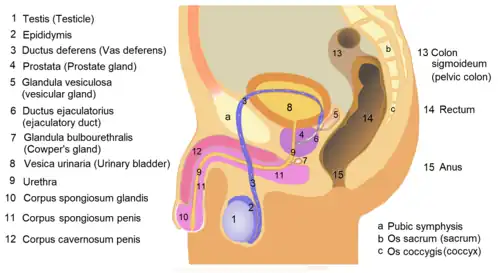

Cross-section of the lower abdomen in a male, showing parts of the urinary tract and male reproductive system, with the seminal vesicles seen top right | |

The seminal vesicles (also called vesicular glands[1] or seminal glands) are a pair of convoluted tubular accessory glands that lie behind the urinary bladder of male mammals. They secrete fluid that largely composes the semen.

The vesicles are 5–10 cm in size, 3–5 cm in diameter, and are located between the bladder and the rectum. They have multiple outpouchings, which contain secretory glands, which join together with the vasa deferentia at the ejaculatory ducts. They receive blood from the vesiculodeferential artery, and drain into the vesiculodeferential veins. The glands are lined with column-shaped and cuboidal cells. The vesicles are present in many groups of mammals, but not marsupials, monotremes or carnivores.

Structure

The human seminal vesicles are a pair of glands in males that are positioned below the urinary bladder and at the end of the vasa deferentia, where they enter the prostate. Each vesicle is a coiled and folded tube, with occasional outpouchings termed diverticula in its wall.[2] The lower part of the tube ends as a straight tube called the excretory duct, which joins with the vas deferens of that side of the body to form an ejaculatory duct. The ejaculatory ducts pass through the prostate gland before opening separately into the verumontanum of the prostatic urethra.[2] The vesicles are between 5–10 cm in size, 3–5 cm in diameter, and have a volume of around 13 mL.[3]

The vesicles lie behind the bladder at the end of the vasa deferentia. They lie in the space between the bladder and the rectum; the bladder and prostate lie in front, the tip of the ureter as it enters the bladder above, and Denonvilliers' fascia and the rectum behind.[3]